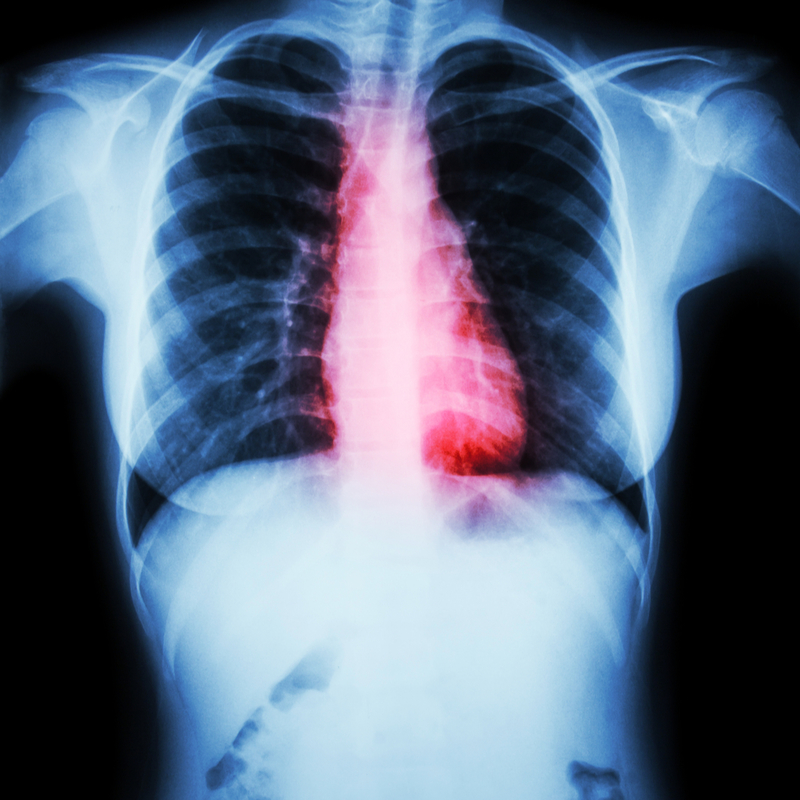

“As in many areas of cardiology, imaging plays a very important role in the management of congenital heart disease, but its function can often be different in congenitally malformed hearts compared with acquired cardiology, partly due to anatomical anomalies and partly because of haemodynamic challenges.”

“We regularly see complex lesions that are unique—defects can be categorised but, within each specific diagnosis, there is wide variation. Imaging is essential to help individualise the management approach.”

Regarding the imaging techniques used, Dr. Bharucha is keen to mention that while echocardiography is still the primary modality for imaging congenital heart disease, other techniques are being increasingly used due to technological advances. “There is greater uptake of computed tomography (CT) and cardiovascular magnetic resonance (CMR) than in previous years,” she explains. “These modalities are much more accessible—the radiation dose with CT is acceptably low for use in small babies and the faster speed of CMR sequences means that a general aesthetic is not always necessary for children.”